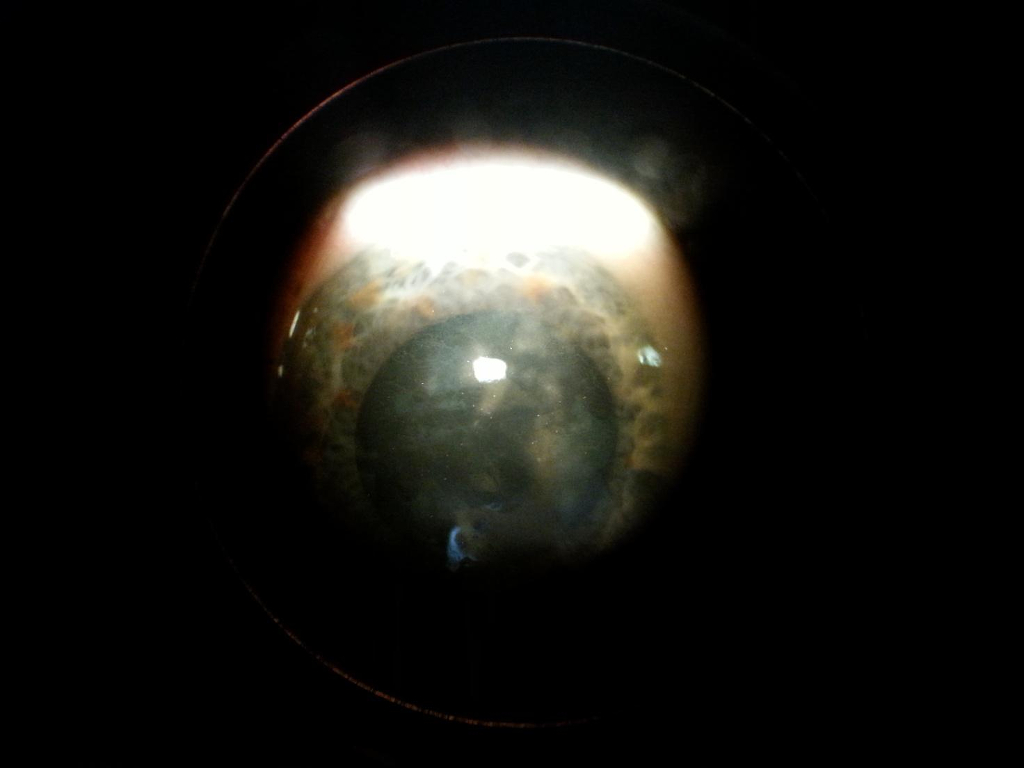

4 Haze (cicatrice o leucoma) corneale post PRK con laser ad eccimeri

Paziente di 50 anni ha effettuato un intervento per correzione di miopia con laser ad eccimeri con tecnica PRK.

Riferisce progressivo calo del visus con annebbiamento, la paziente inoltre riferisce difficoltà nel lavoro quotidiano al computer ed impossibilità alla guida dell’autovettura.

L’obiettività oculistica è la seguente:

visus occhio destro: 2-3/10 con correzione ottica

visus occhio sinistro 2/10 con correzione ottica

biomicroscopia: haze corneale centro paracentrale (vedi foto)

Programmato intervento di PTK (cheratectomia fototerapeutica) con laser ad eccimeri con lo scopo di regolarizzare la superficie corneale e ridare trasparenza alla cornea asportando l’haze.

In attesa dell’intervento nel periodo estivo per consentire una buona qualità di vita sono state provate delle lenti a contatto (vedi foto) che hanno assicurato una vista sufficiente per le attività quotidiane della paziente.